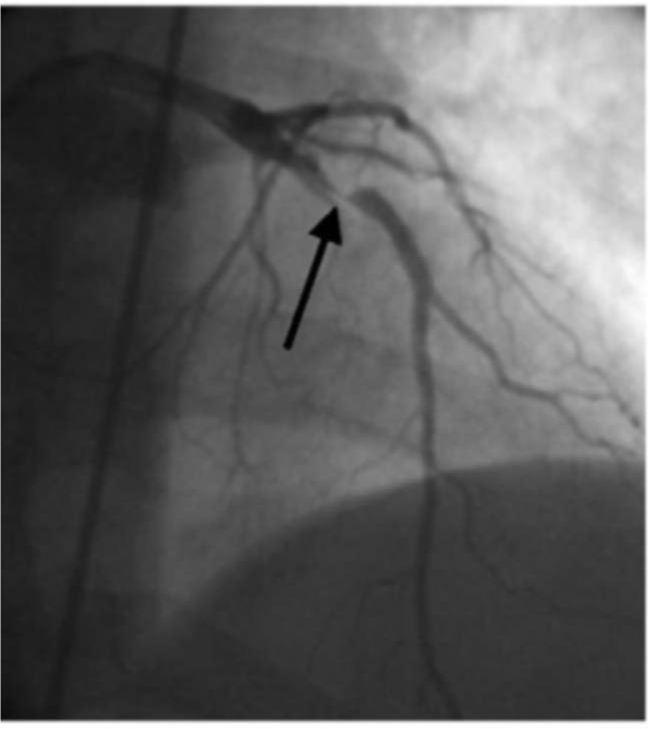

Electrocardiographically, patients have very characteristic patterns: symmetrical inversion and, sometimes, deep T-waves in precordial leads, especially in V3-V4, although these features may extend to all precordial leads. Wellens syndrome is associated with a critical stenosis of the left anterior descending coronary artery (LAD) (Figure 7).13,14

Figure 7 In the angiographic image we can see how there is a severe occlusion in the upper third of the anterior descending coronary artery (greater than 95%).

Perhaps the most important aspect of this pattern or syndrome is the great capacity it has to develop in less than 10 days (after identification by electrocardiogram) a massive myocardial infarction in the anterior wall of the ventricle (Figure 8). The electrocardiographic pattern of "short PR interval alongside a short QT interval” was described by Breijo et al. in 2008.1,2 It ischaracterized by the presence in the electrocardiogram of a PR interval of less than 0.120 seconds alongside a QT interval of less than 0.400 seconds (Ie, a reduction in the duration of cardiac electric systole1 and that over 80% cases, are accompanied by syncopal events, nocturnal tachycardias and, sometimes, ventricular fibrillation and, even, sudden death.

Figure 8 In the angiographic image we can see how there is a severe occlusion in the upper third of the anterior descending coronary artery (greater than 95%).